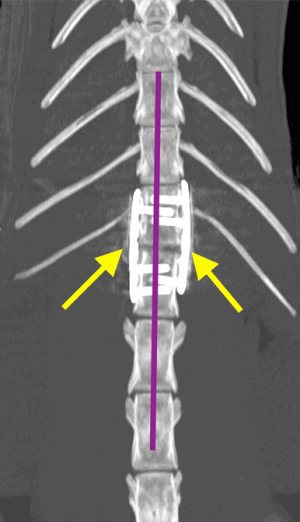

Osiris was assessed by our anaesthesia team and nurses who stabilised him so that he could be anaesthetised. Under a general anaesthetic, a CT of the back confirmed the fracture in his spine (red arrow on images below). The vertebral canal (green star) is where the spinal cord runs. The floor of the vertebral canal (blue lines) should be level and as you can see in the images there is a step in the floor, resulting in pressure on the spinal cord. The image on the right also shows a deviation in the spine (the purple lines should be straight), also adding pressure to the spinal cord. This pressure means that the neurotransmission pathway between the brain and legs is disrupted, which ultimately meant that Osiris couldn’t use his hindlimbs.

The surgeon involved (Andy Craig) recommended surgery and the clients wanted to proceed. Osiris was taken to theatre where the vertebra were approached through an incision in his back. Some of our surgical interns and neurology resident (Miguel Benito) assisted Andy and the vertebra were put back into a normal position with two metal plates and screws (yellow arrows in images below) used to stabilise the fracture. These implants will keep everything stable while the fracture heals. A CT scan was taken after the surgery and confirmed normal alignment. In the images below you can see the floor of the vertebral canal is level (blue line) and that there is no bend in the vertebra (purple line).